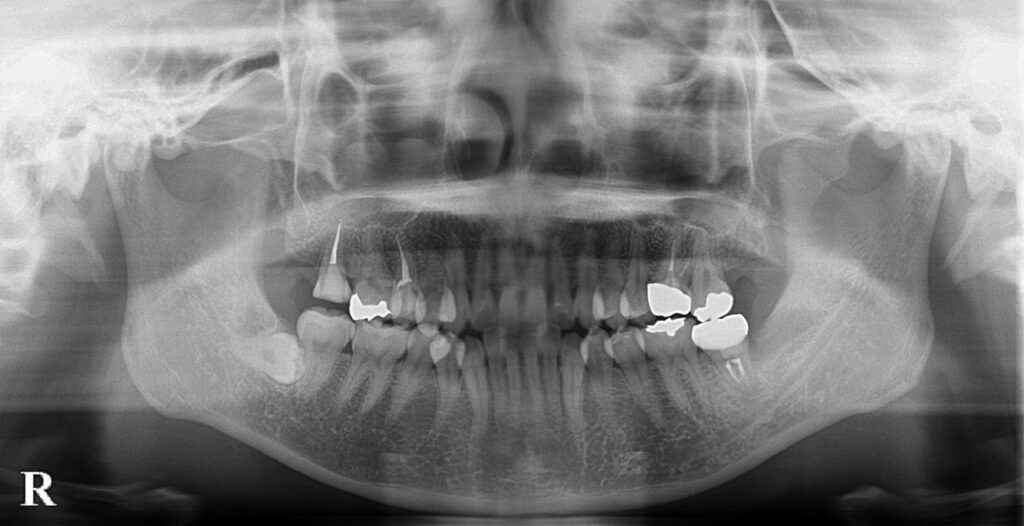

現在最終補綴をおこない経過をみている状態ですがしっかり生着している状態がレントゲンからもわかります。